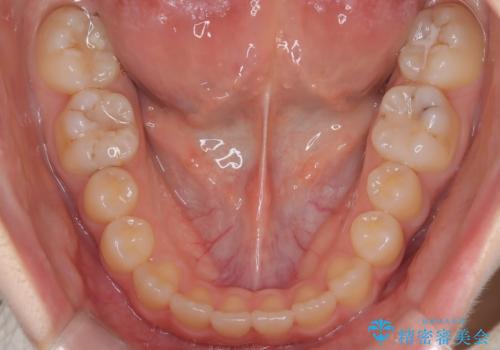

- 前歯のガタツキが気になるとのことで来院されました。

前歯のガタツキに加え、奥歯の噛み合わせにも問題があったため、マウスピース矯正で治療し改善しました。